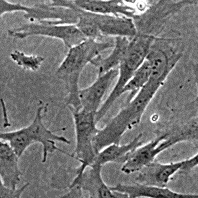

<b>Морфология</b>: фибробластоподобная<br>

<b>Способ культивирования</b>: монослойный<br>